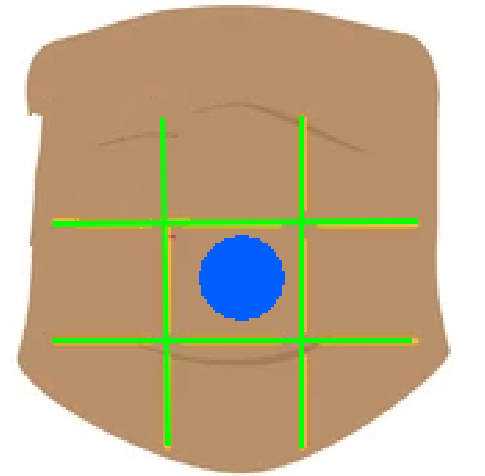

Right hypochondriac region

Left hypochondriac region

Epigastric region

Right lumbar region

Left lumbar region

Umbilical region

Right inguinal region

Left inguinal region

Hypogastric regions